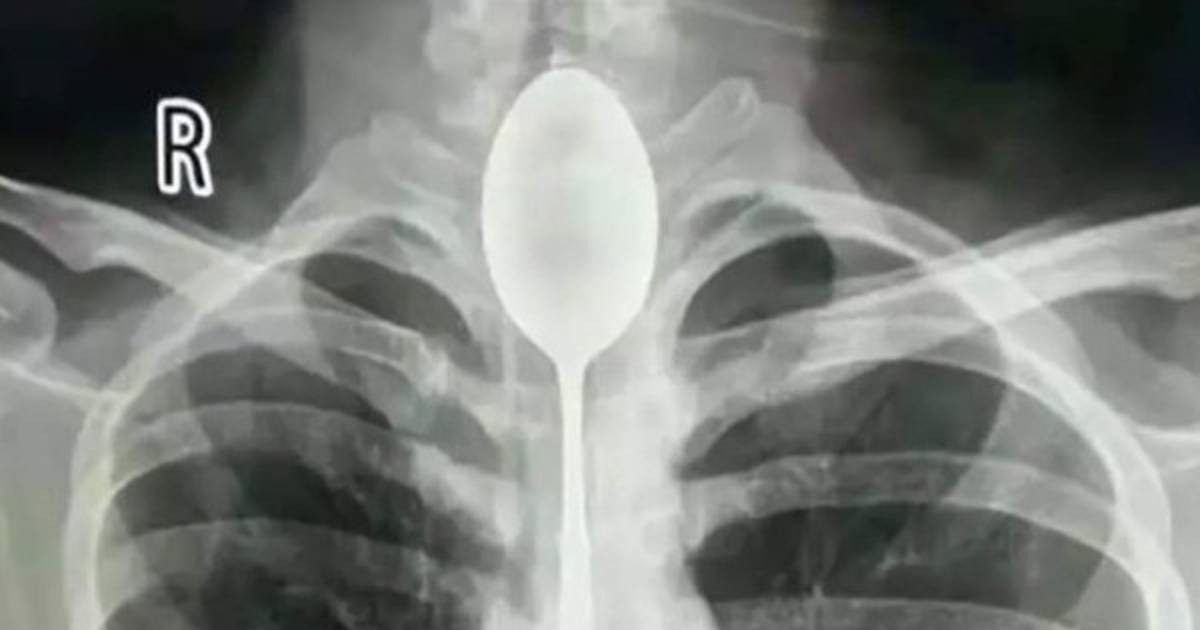

El hombre, de apellido Zhang, llegó al Hospital General de Xinjiang con dolores en el pecho y los doctores se sorprendieron al conocer que llevaba con la cuchara ahí por un año.

Los doctores quedaron impactados por el caso y admitieron que nunca antes habían visto algo similar. Sostuvieron que cuando recibieron al paciente, su esófago 'ya estaba infectado'.

El paciente relató que se tragó la cuchara hace un año, cuando hizo una apuesta con sus amigos en estado de embriaguez. Sin embargo, falló al intentar sacarse con una cuerda el cubierto.

El joven tuvo que asistir al hospital después de sufrir un golpe en el pecho, lo que agravó su estado. Afirmó que no acudió antes porque no había experimentado problemas a la hora de comer.